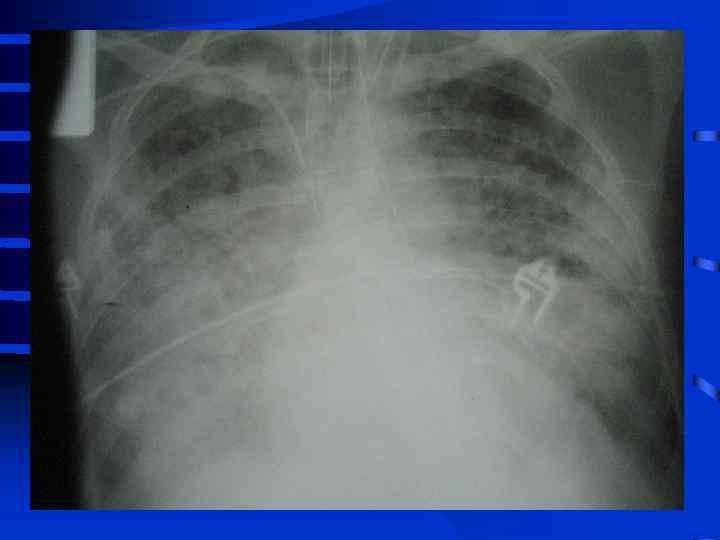

• I стадия Все изменения носят умеренный характер, индекс оксигенации (Pa. O 2/Fi. O 2) более 300, Pa. CO 2 снижен до 34 - 32 мм. рт. ст. , рентгенографически полнокровие легких, ячеистая деформация на фоне усиленного легочного рисунка. • II стадия Повторное, часто резкое ухудшение состояния. Психические нарушения (беспокойство, неадекватность), тахикардия свыше 110 - 120 в мин. , АД сист. более 150 мм. рт. ст. , индекс оксигенации менее 250 - 200, артериальная гипокапния. Рентгенографически - появление мелкоочаговых теней на периферии

• III стадия необходима респираторная поддержка, сознание нарушено, индекс оксигенации менее 200, шунтирование 30 - 50% от величины МОК. Появляются признаки полиорганного поражения: нарушение функции кишечника (парезы, острые язвы) • и почек (эпизоды олигурии) • Рентгенографически - сливные тени, иногда первые признаки гидроторакса